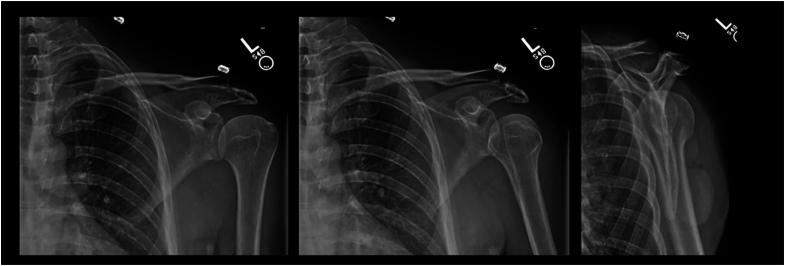

Acromion fracture associated with traumatic first time anterior shoulder dislocation: a case report.

JSES Rev Rep Tech. 2023 Dec 16;4(2):284-290. doi: 10.1016/j.xrrt.2023.11.002. eCollection 2024 May.

Acromion fracture associated with traumatic first time anterior shoulder dislocation: a case report.首次创伤性肩关节前脱位伴肩峰骨折:一例报告